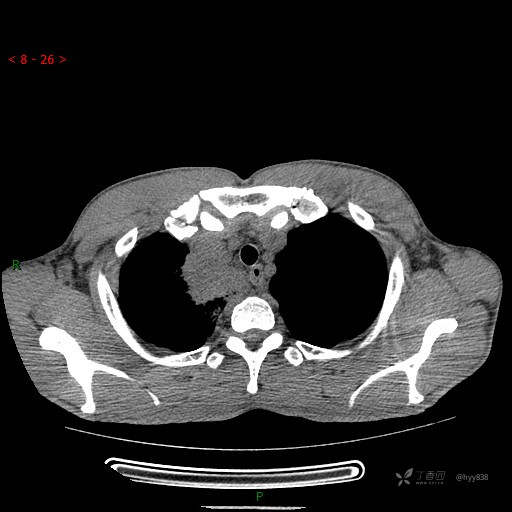

静脉期